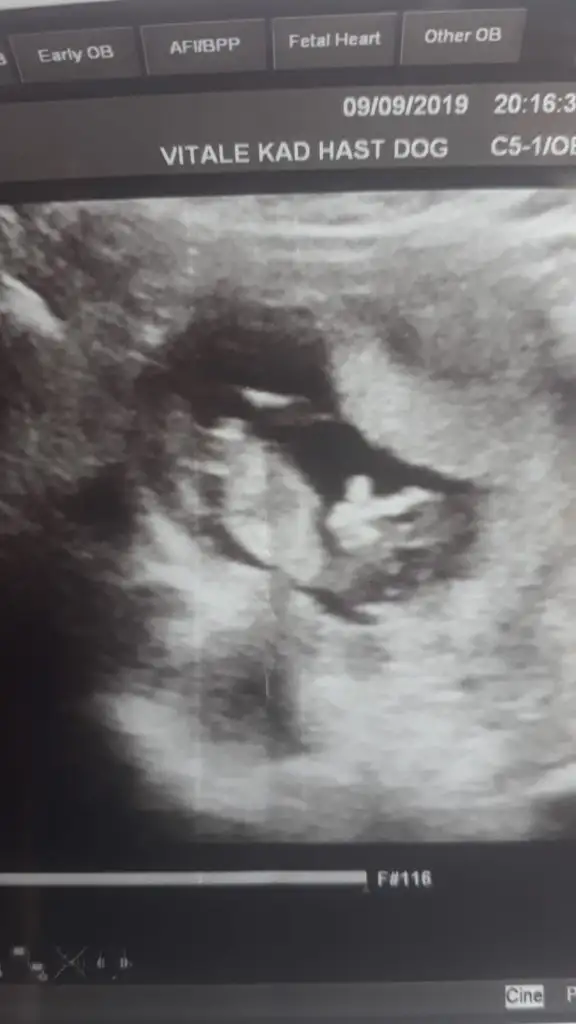

Kız gibibir fotograf karesi de bizden gelsin dr.henuz tahmin yapmadi siz neler goruyoyorsunuz

bir fotograf karesi de bizden gelsin dr.henuz tahmin yapmadi siz neler goruyoyorsunuz

bir kiz bir erkek cevabi geldierkeğe benziyor sanki canım